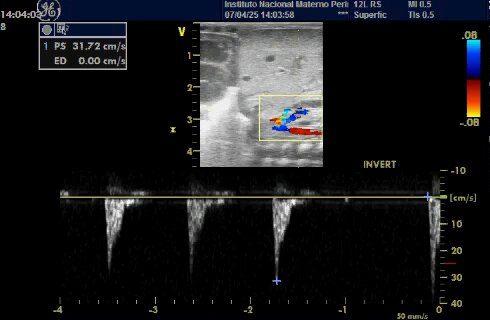

DOPPLER RENAL DE ALTA RESISTENCIA Y FLUJO REVERSO EN UN PACIENTE CON PERSISTENCIA DEL DUCTUS ARTERIOSO CON REPERCUSION HEMODINAMICA.

SHOCK CARDIOGENICO SECUNDARIO A SOBRECARGA HIDRICA DEBIDO A PERSISTENCIA DE DUCTUS ARTERIOSO GRANDE